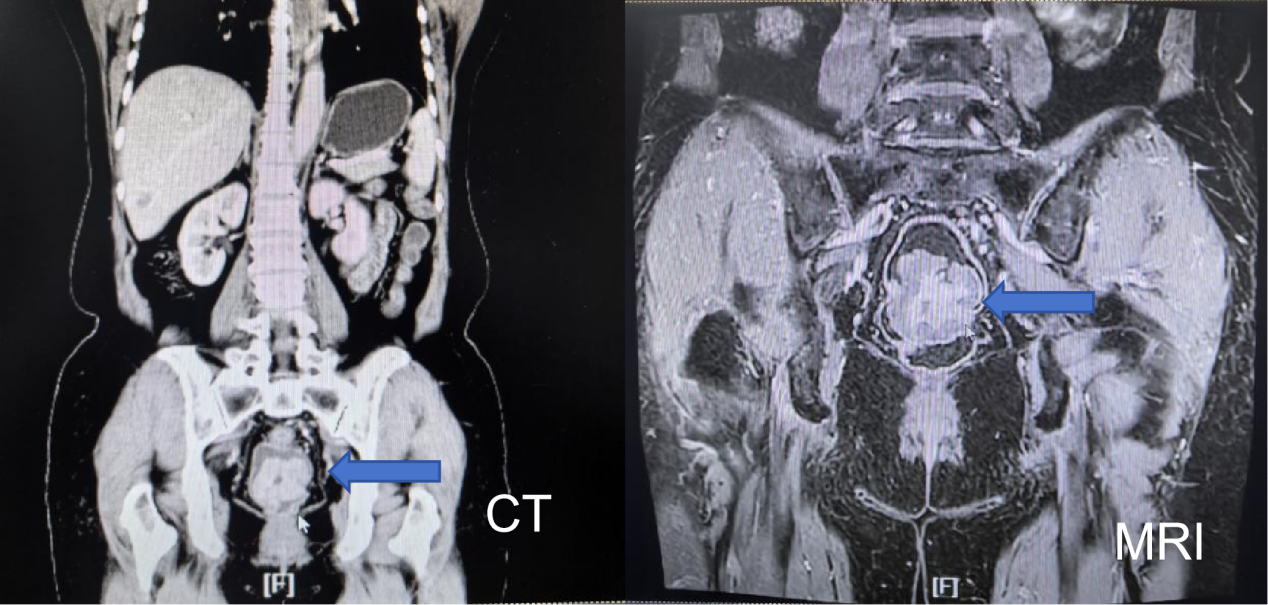

转至胃肠外科二病区后,病区医护立即为患者启动全面术前评估:全腹部增强CT显示直肠局部团块影符合腺瘤改变,同时伴子宫后壁肌瘤伴钙化;MRI检查进一步提示直肠中段肿块,考虑直肠绒毛状管状腺瘤伴癌变T3N1,CRM(+),EMV(+),且合并子宫多发肌瘤。然而,核心的恶性肿瘤诊断却遭遇瓶颈——再次、三次行肠镜下大块、深挖活检后,仍未能明确确诊。诊断的不确定性、直肠病变与子宫肌瘤的合并存在,让诊疗方案的选择陷入两难。